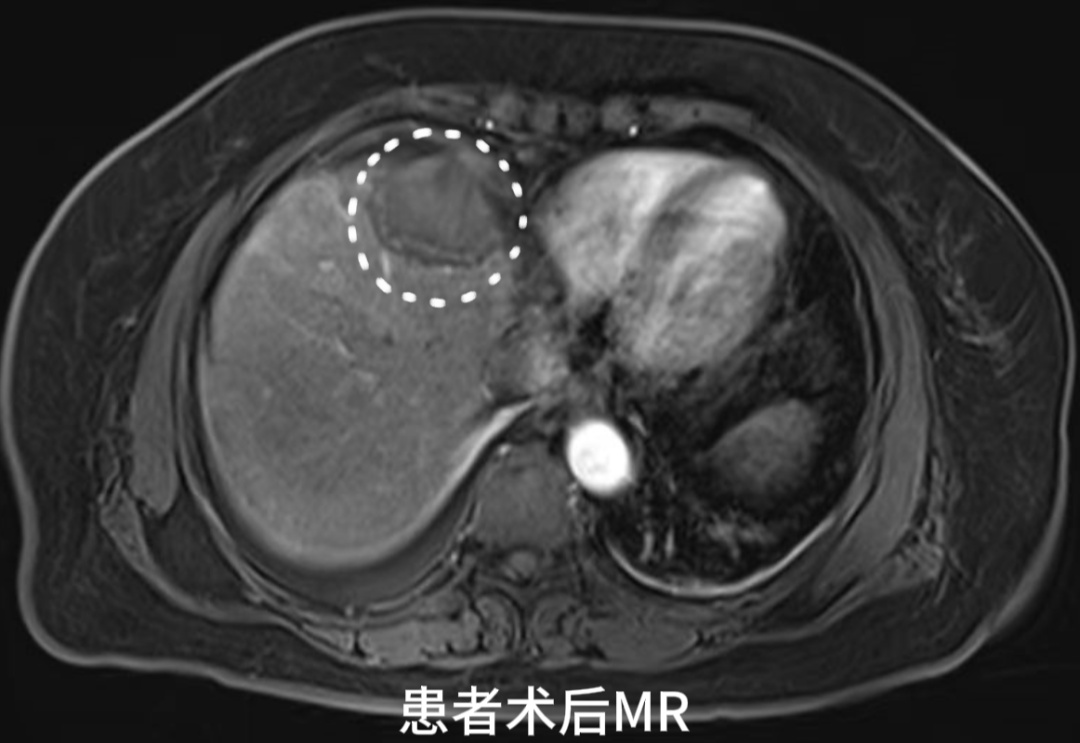

患者术后第二天MR

复查结果提示未见肝内有强化病灶,肿瘤完全失去了活性。经外周静脉注射造影剂Sonazoid后,病灶区域始终未灌注区,显示消融效果满意。